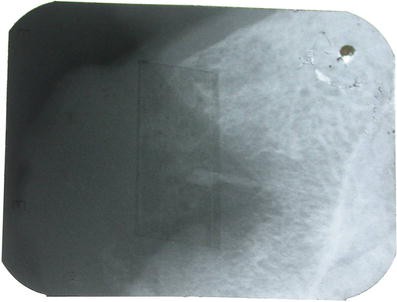

Involvement of the underlying bone in panoramic radiography

In periapical radiography radiolucent bone resorption with nonsclerotic and well-defined borders and 2 × 3 cm under the tumor-like lesion